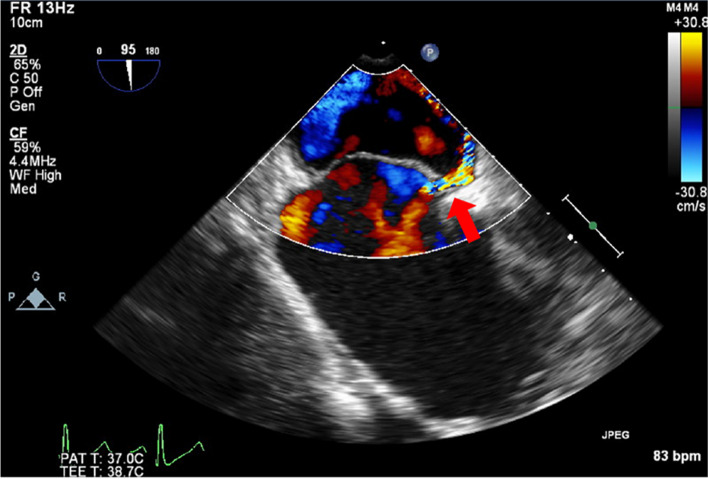

Case presentation: A 66-year-old man with interstitial pneumonia underwent OPCAB. Preoperative transesophageal echocardiography revealed right-to-left shunt flow through a PFO induced by the Valsalva maneuver. During OPCAB, heart displacement resulted in right-to-left shunting and acute hypoxemia, which quickly improved with increase of inspired oxygen fraction. After chest closure, bidirectional shunt flow developed under increased airway pressure.

Conclusions: Vigilant intraoperative monitoring with TEE and postoperative airway pressure management are important to address shunt flow and hypoxemia due to PFO.